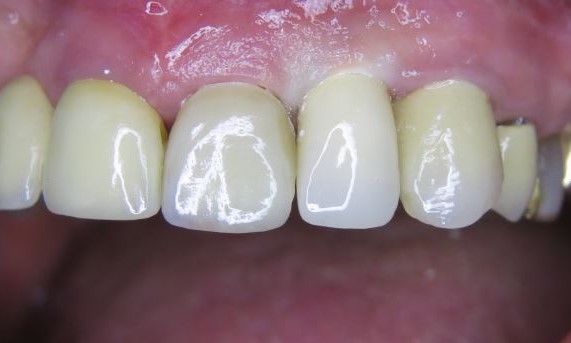

Exzellente Ästhetik

Langfristiger marginaler Knochenerhalt für eine exzellente Ästhetik über Jahre hinweg. Sie wissen, dass Sie gewonnen haben, wenn Ihr anspruchsvollster Patient dauerhaft zufrieden ist.

Langfristiger Knochenerhalt und exzellente Ästhetik dokumentiert und klinisch erprobt.